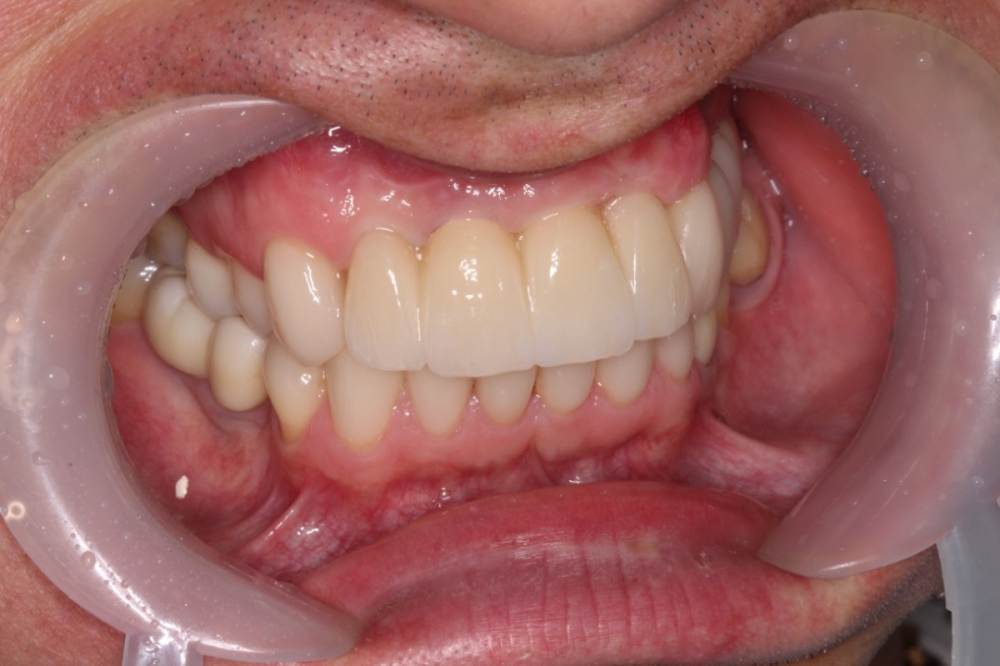

maksimstom Опубликовано 1 сентября, 2021 Автор Поделиться Опубликовано 1 сентября, 2021 Всем спасибо! Результат через 6 мес, 2 пластики десны 4 1 3 Ссылка на комментарий

Irouil Опубликовано 1 сентября, 2021 Поделиться Опубликовано 1 сентября, 2021 Как решили? учитывая исходник - очень внушительно! Ссылка на комментарий

maksimstom Опубликовано 2 сентября, 2021 Автор Поделиться Опубликовано 2 сентября, 2021 Тоннельно 1 транспл окклюзионно, 1 вестибулярно, ждал месяца 4, бугор подрос 1 Ссылка на комментарий